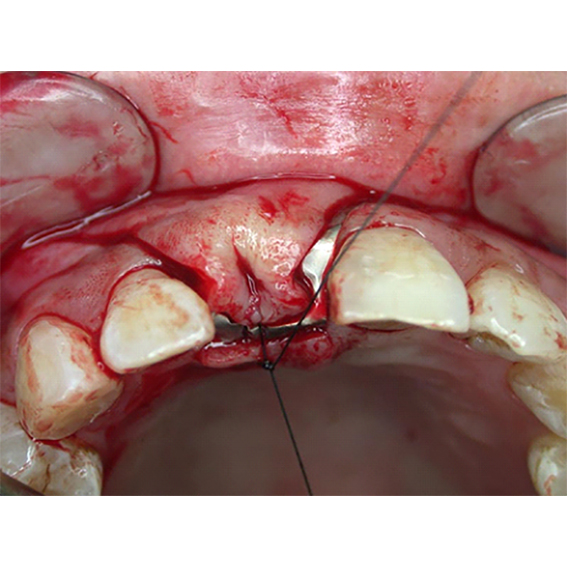

Pure titanium membrane of ultra-thin thickness of about 10 microns (0.01mm). Totally inert, biocompatible and non-biological thus removing the fear of disease transmission from collagen of bovine source. It allows ease of handling and adaptation over the operative site. Because of its mouldability, it does not require pin or screw fixation, thus avoiding the risks of pin or screw swallowing or aspiration. Excellent clinical performance in guided tissue regeneration. Resistance to infection after exposure. Primary wound closure is not necessary. No tissue reaction or wound infection.